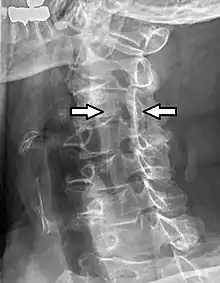

| C5-C6, followed by C6-C7, is the most common location for radiculopathy in the neck. | |